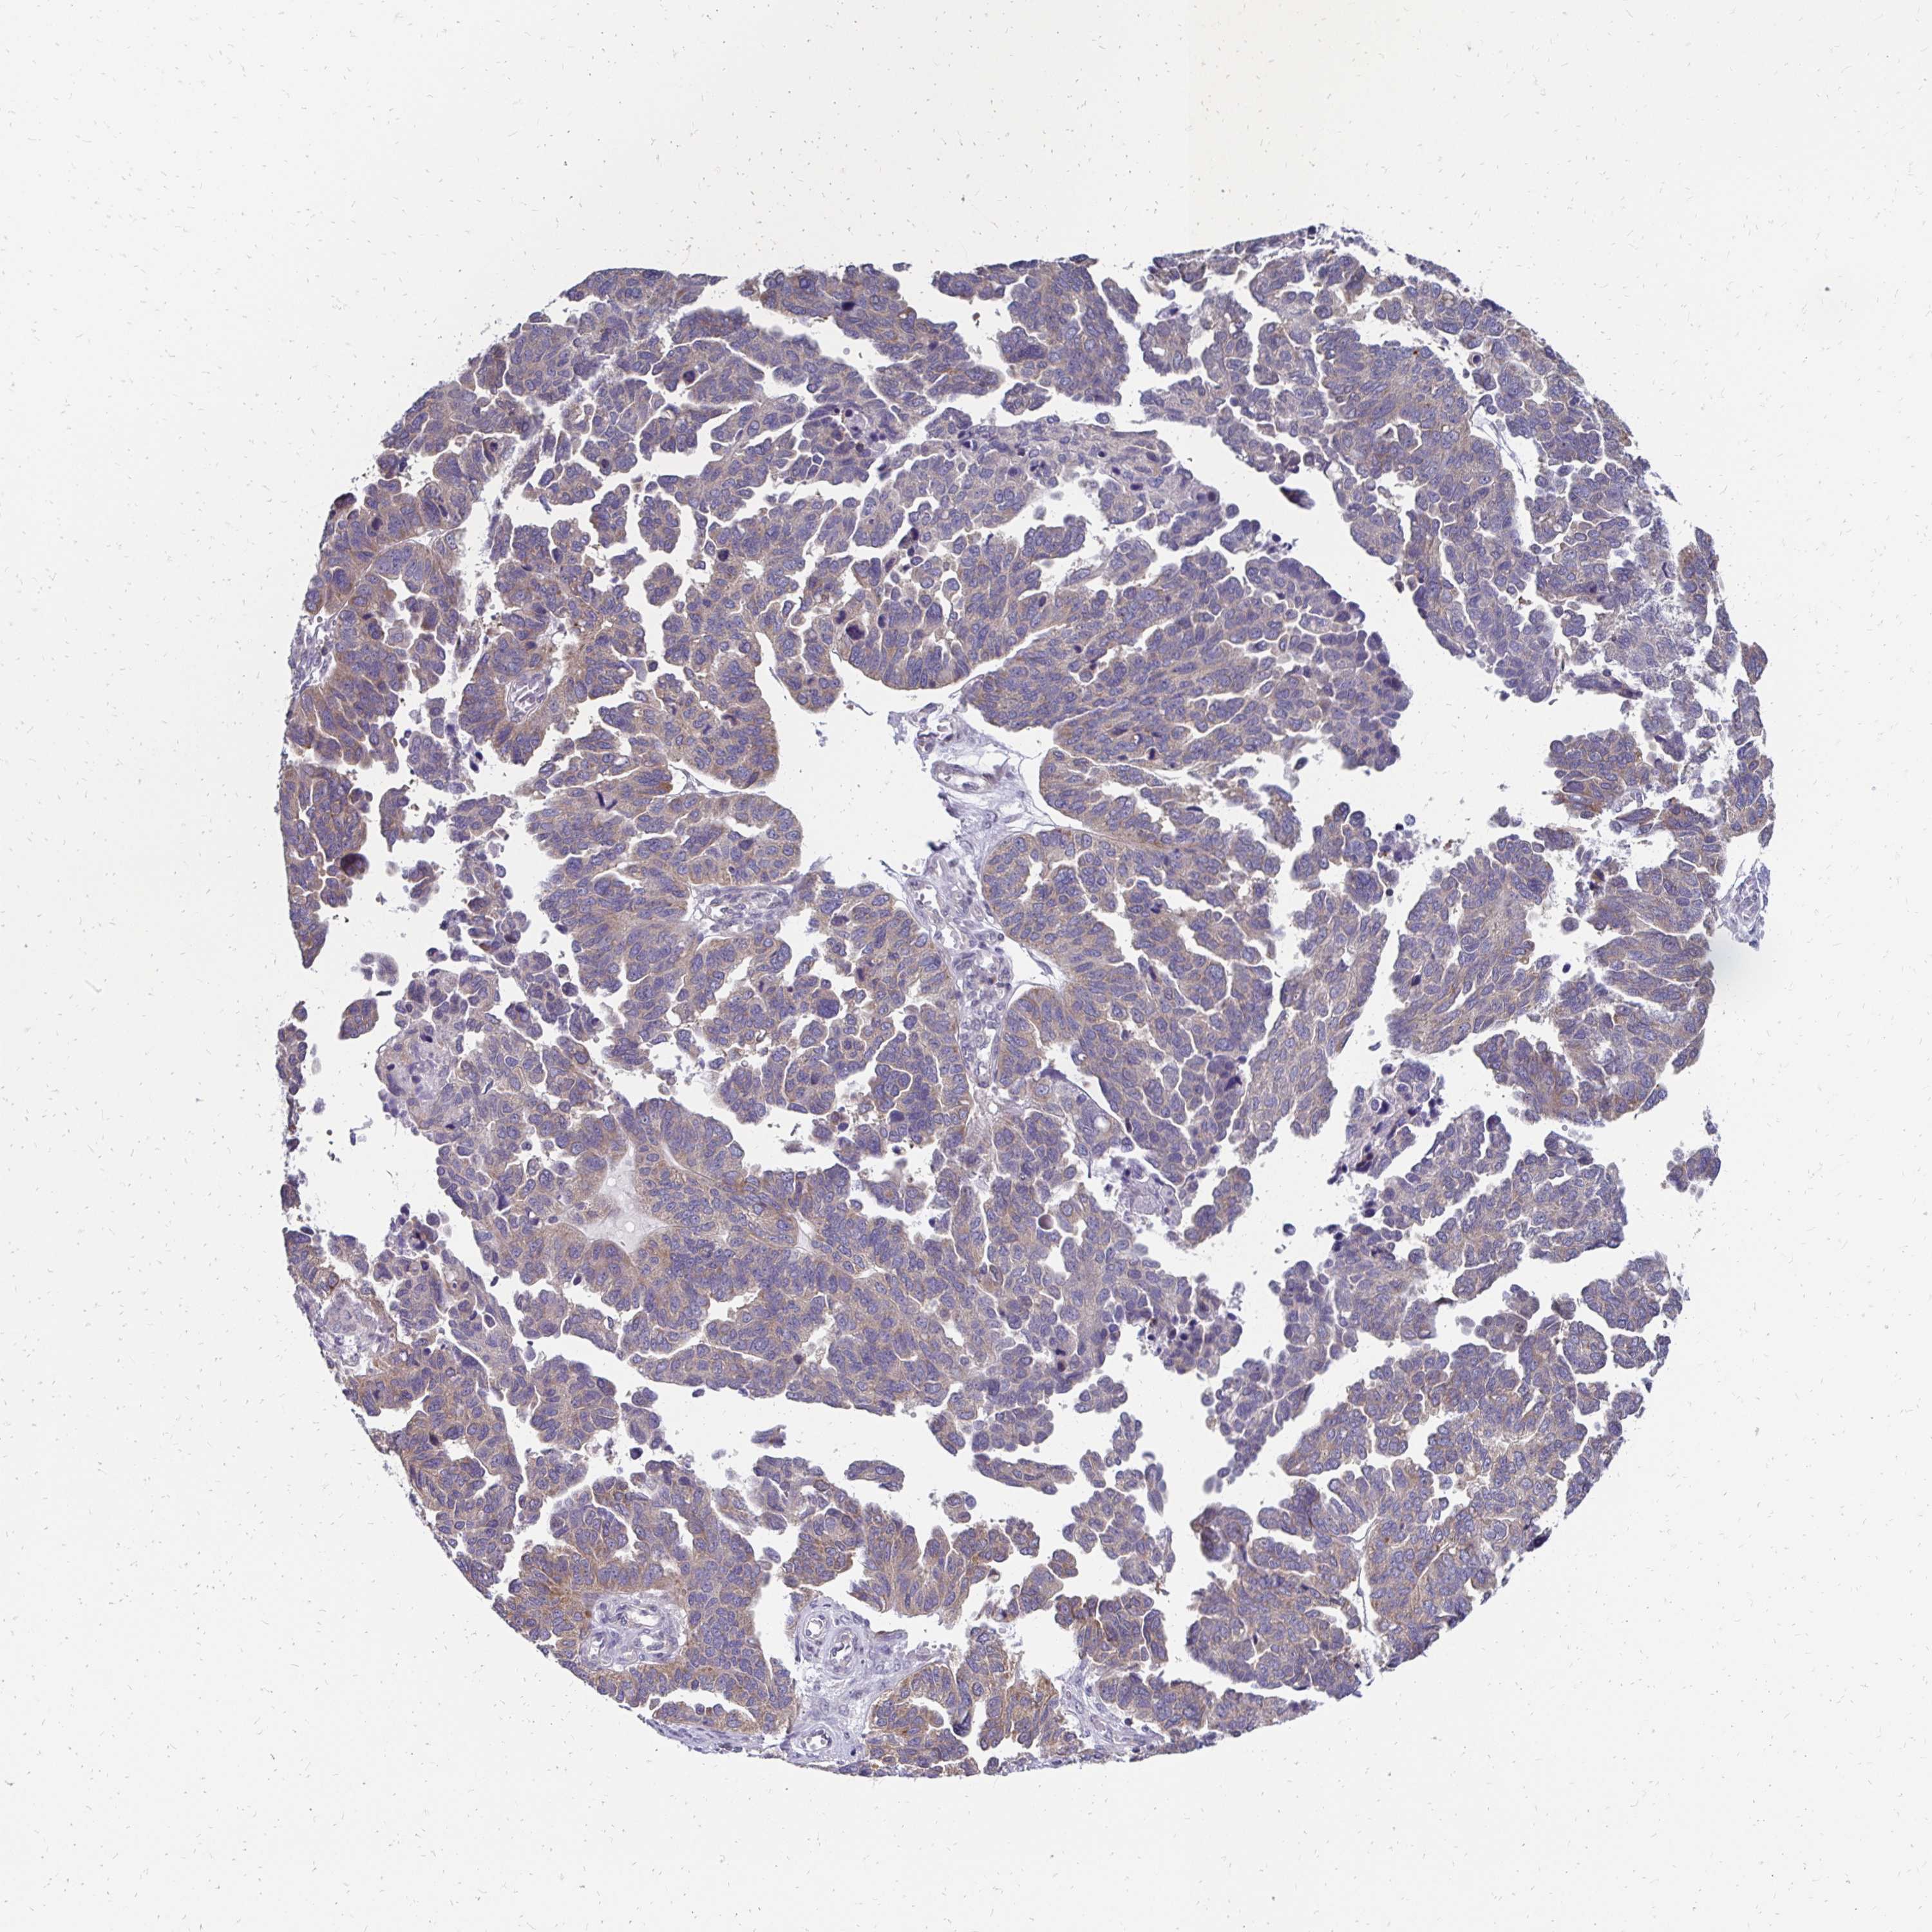

OVARIAN CANCER - Protein expressioni

A mouse-over function shows sample information and annotation data. Click on an image to view it in a full screen mode. Samples can be filtered based on level of antibody staining by selecting one or several of the following categories: high, medium, low and not detected. The assay and annotation is described here.

Note that samples used for immunohistochemistry by the Human Protein Atlas do not correspond to samples in the TCGA dataset.

Antibody stainingi

Antibody staining in the annotated cell types in the current human tissue is reported as not detected, low, medium, or high, based on conventional immunohistochemistry profiling in selected tissues. This score is based on the combination of the staining intensity and fraction of stained cells.

Each image is clickable and will lead to virtual microscopy that enables deeper exploration of all samples and also displays staining intensity scores, fraction scores and subcellular localization as well as patient and tissue information for each sample.

Antibody HPA048677

Antibody CAB011574

Staining

High

Medium

Low

Not detected

Intensity

Strong

Moderate

Weak

Negative

Quantity

>75%

75%-25%

<25%

None

Location

Nuclear

Cytoplasmic/membranous

Cytoplasmic/membranous,nuclear

Cystadenocarcinoma, mucinous, NOS

Adenocarcinoma, NOS

Carcinoma, endometroid

Carcinoma, NOS

Cystadenocarcinoma, serous, NOS